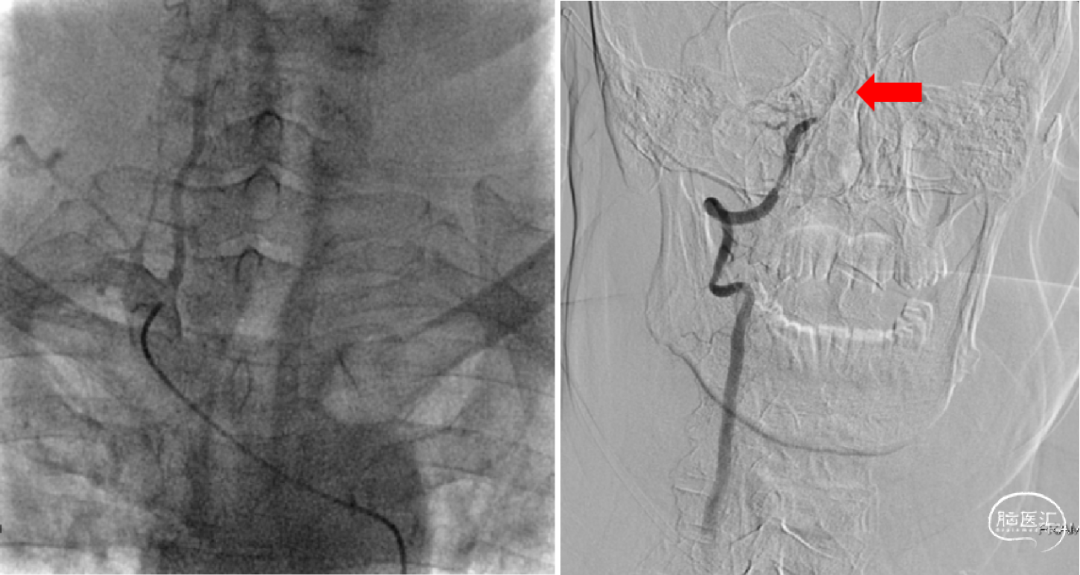

1、选择2×15mm球囊针对狭窄处进行亚满意扩张;2、术后造影,狭窄好转,远端血流明显改善,观察15分钟后未见明显变化后结束手术。